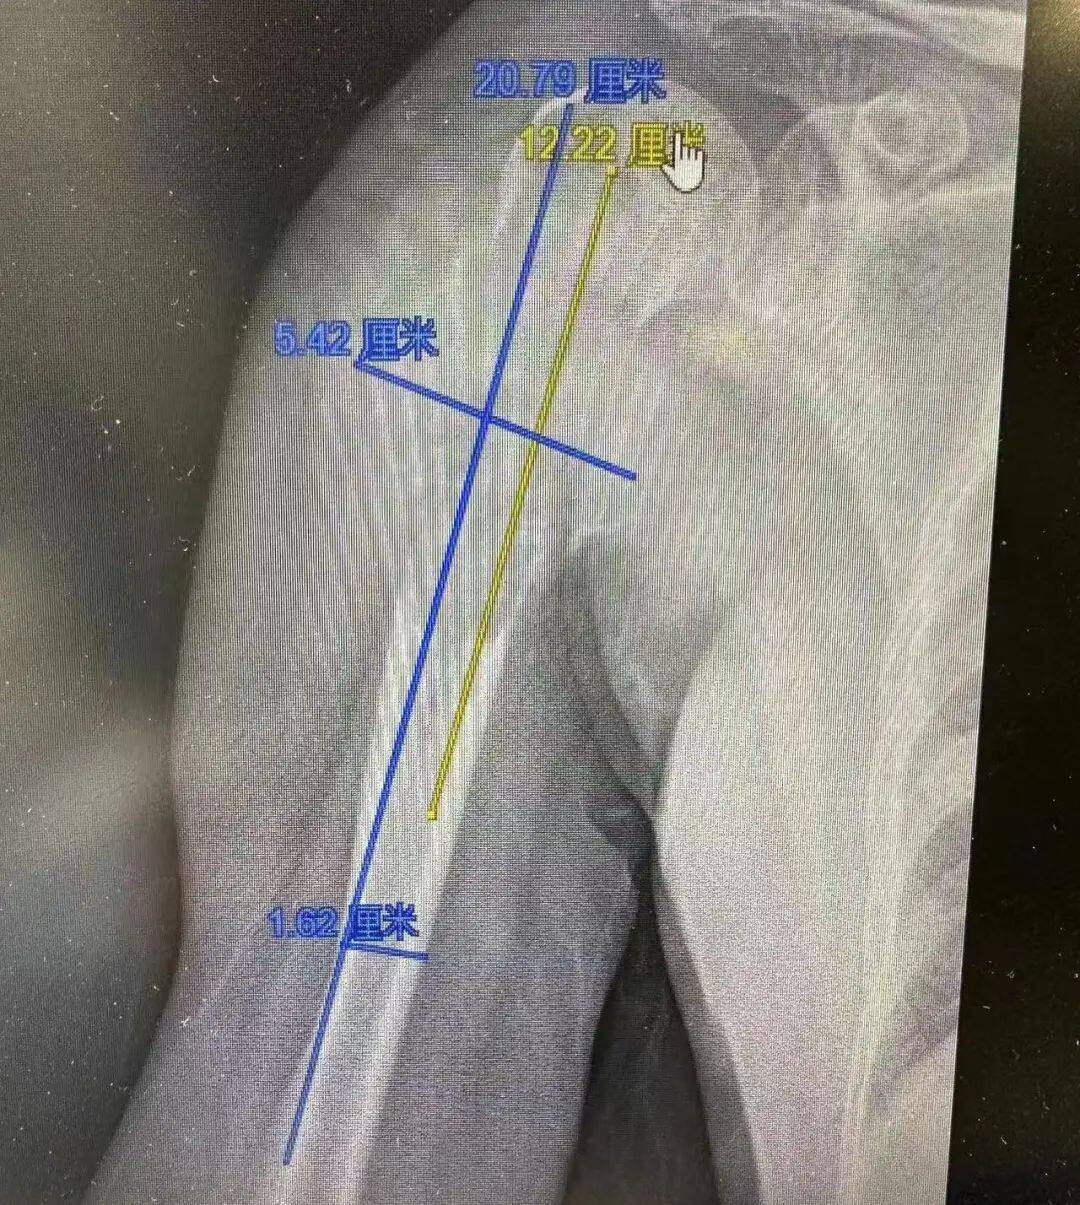

邓爱东接诊后,为曹阿姨安排了严谨细致的检查,根据肿瘤病史、骨折特征、影像学检查、肿瘤指标检测,结果提示曹阿姨的右肱骨颈至肱骨上段出现占位性病变,诊断为右肱骨骨肿瘤,并伴随病理性骨折,导致她右肩功能严重受限。通过对肱骨近端瘤段进行精确测量,确认瘤段长度达12厘米,宽5.5厘米。

“瘤段切除将影响上臂功能,甚至导致整个上臂无法支撑,因此必须进行骨缺损显微重建。”邓爱东说道。然而,传统的肩关节假体置换术因曹阿姨瘤段缺损范围过长而难以实施。面对这一难题,经过肿瘤科、医学影像科、核医学科等多学科专家深入讨论与评估,最终决定采用肱骨骨肿瘤切除术+带血管蒂腓骨瓣游离移植重建肱骨骨缺损术,以恢复曹阿姨的上肢功能。